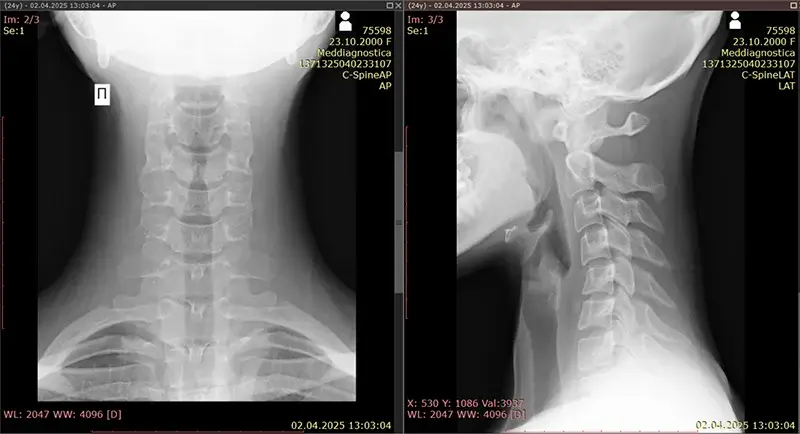

Ми робимо низку рентгенівських знімків з різних кутів та положень, щоб забезпечити точне вимірювання відсотка втрати лордозу в шийному відділі хребта та всіх аномальних викривлень хребта (робиться до та після лікування для порівняння).